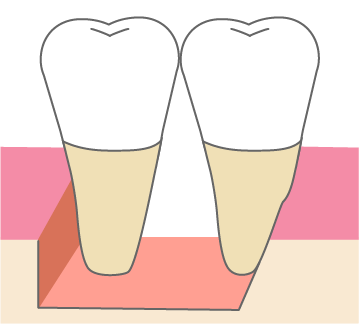

歯周組織再生療法は施術の難易度が高く、ほとんどの歯科では扱っていない内容です。

専門医資格を持つ医師が歯周組織再生治療を手がけるので、安心して治療を受けていただけます。